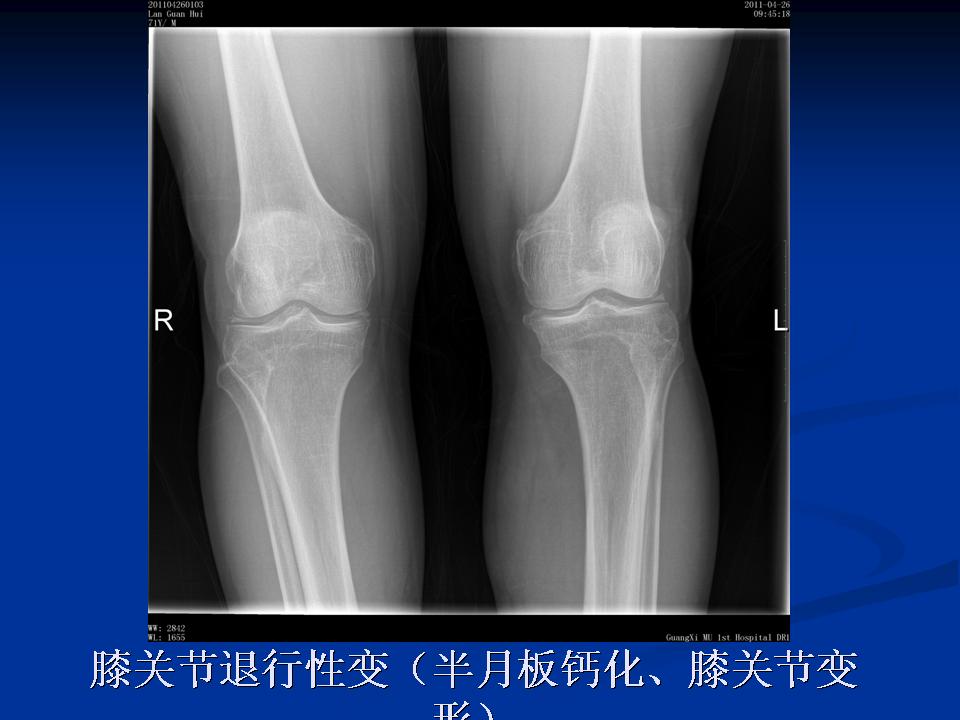

影像学检查 X线 四个方向X线影像 l 早期可无改变 l关节间隙变窄、不均匀、消失(成人<3mm; 老年人<2mm)。 l骨赘形成 l关节内游离体、骨质疏松 l软骨下骨板硬化、囊性变

膝关节退行性变(半月板钙化、膝关节变形)